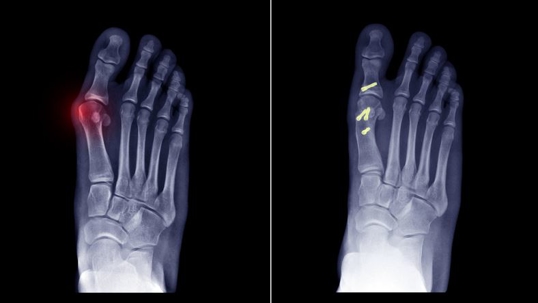

Cartiva Big Toe Joint Implant Complications

Foot xray

Some patients who have complications from a big toe implant may actually be suffering due to the type of implant used in the surgery. The Cartiva Big Toe Joint implant has been used in recent years as an option to toe fusion surgery when treating the painful conditions of hallux rigidus, hallux limitus, and osteoarthritis in the big toe. Concern has arisen recently with medical studies and/or surgical results showing that the Cartiva implant may only be effective in about half of the cases. Failures appear to be due to a defect in the design of this synthetic cartilage implant. These Cartiva implant failures often result in patients undergoing a revision surgery to remove the device. Sometimes multiple surgeries are required toward the goal of reversing problems from the implant failure.